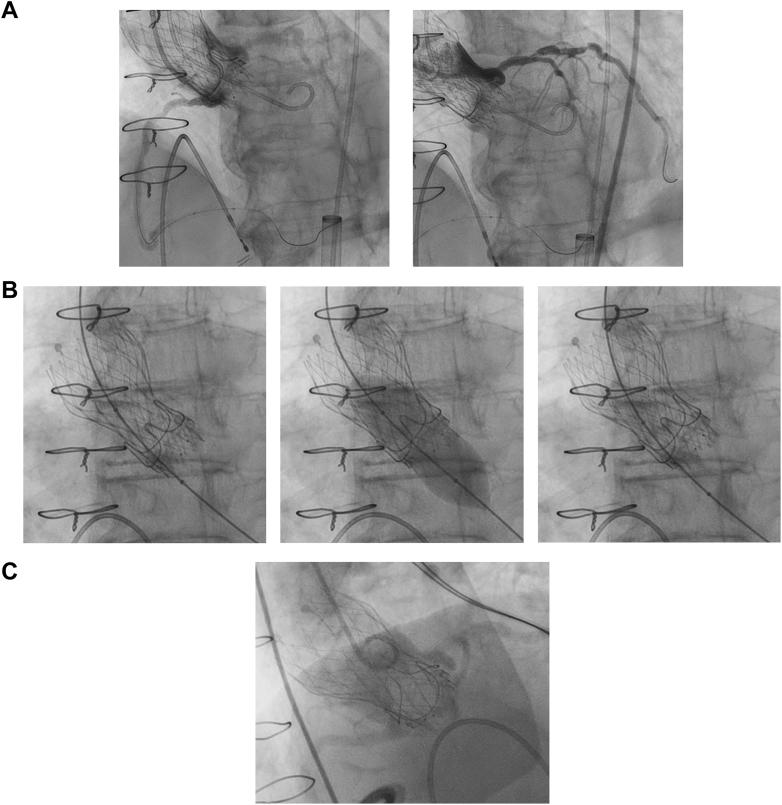

An 85-year-old woman who underwent previous surgical aortic valve replacement (Magna #19 valve, Edwards Lifesciences) presented with severe bioprosthetic stenosis. A TAV-in-SAV procedure was planned using an Evolut FX 23-mm valve (Medtronic) with optimization using a 20-mm balloon, which corresponds to the in vitro waist diameter of the Evolut FX 23-mm valve. Preprocedural CT, including maximum intensity projection (MIP) images, indicated a risk for sinus sequestration. A thorough CT assessment performed on the basis of this plan led to a successful optimized procedure.

Identifying sinus sequestration risk is crucial in TAV-in-SAV. MIP images on CT may help visualize the relationship between the neoskirt and the sinotubular junction. Optimizing TAV expansion is essential, and CT assessment should be conducted on the basis of the planned procedure.